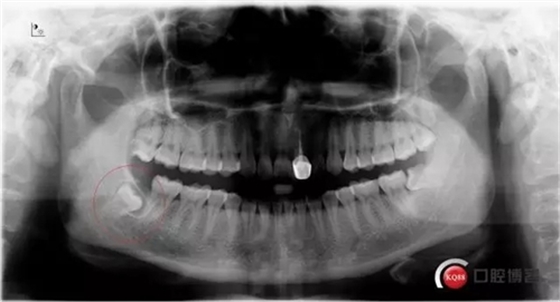

術(shù)前曲面斷層